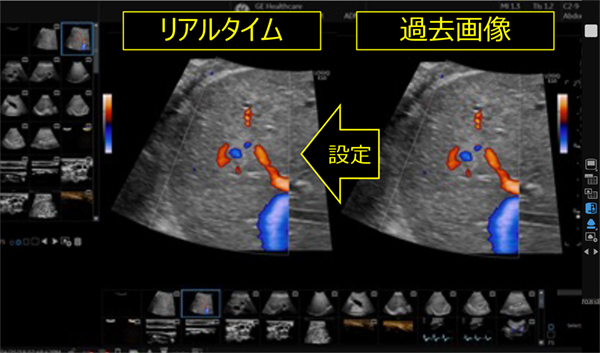

特長<6>

Compare Assistant*

過去画像をすばやく呼び出し,検査中の画像と簡単比較。

RAW Dataでの保存画像であれば,設定条件も瞬時に同じになり,mm単位の比較や血流評価の比較がより簡単に。